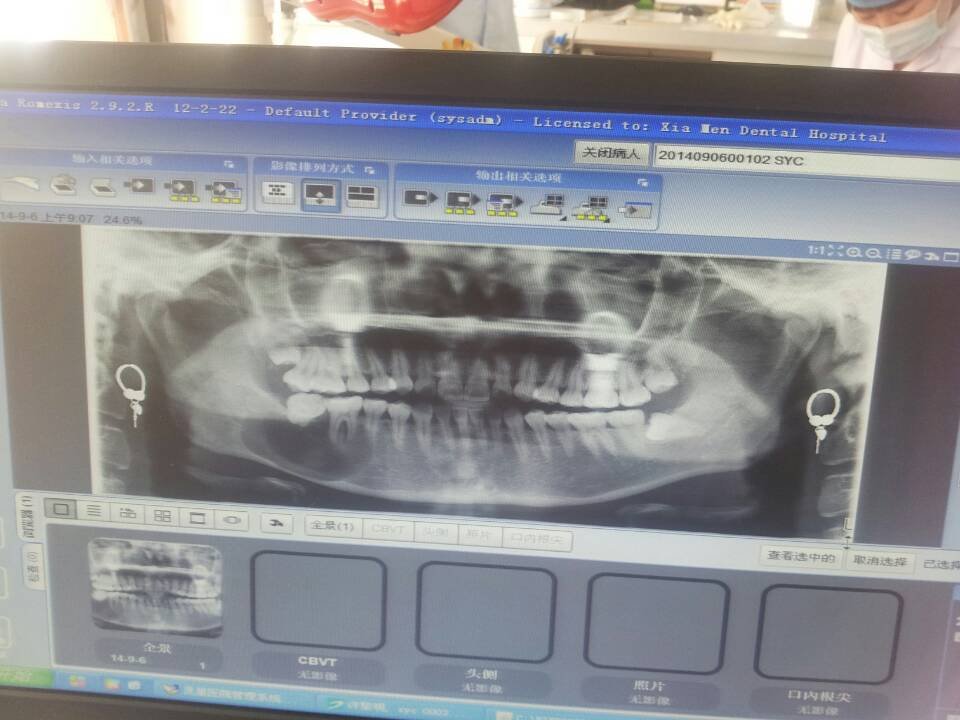

昨天去口腔医院检查牙齿,拍片发现牙齿下面长了个囊肿,医生说需要手术,但是我现在是哺乳期,孩子太小还 昨天去口腔医院检查牙齿,拍片发现牙齿下面长了个囊肿,医生说需要手术,但是我现在是哺乳期,孩子太小还不能断奶。我想知道,除了手术还有没有其他的治疗方法,等孩子大点了再手术。 点击展开 匿名用户 2014-09-07 11:55 为您推荐: 其他回答 手术和哺乳没关系,又不用住院,建议早治疗早康复 匿名用户 2014-09-07 12:04 做手术先 匿名用户 2014-09-07 12:00 囊肿越早治疗越好,拖长了容易病变 匿名用户 2014-09-07 11:59 不能 匿名用户 2014-09-07 11:58 相关问题 我家宝贝的牙齿开始发黑了 不会的,宝宝的牙齿可能是龋坏了,去口腔医院检查吧 啊~生孩子的时候没注意卫生,弄得现在牙齿很黄,想去做美白,有妈妈知道广州哪家口腔医院做牙齿美白好不? 成都有哪些矫正牙齿的医院,成都口腔医院周六上班吗?